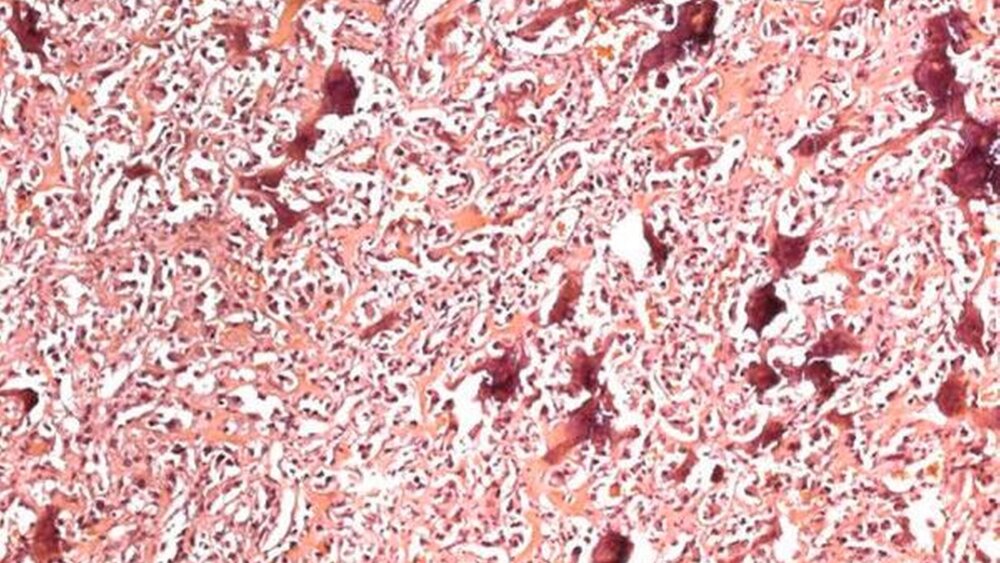

Der histopathologische Befund ergab eine zellreiche Neubildung. Diese bestand in den zentralen Abschnitten aus spindeligen, fibroblastär-differenzierten Zellelementen mit länglichen Zellkernen, die zum Teil auch in Mitose standen. In der Umgebung konnte ein unreifes Osteoid, das von einem einreihigen Osteoblastensaum umgeben wurde, ausgemacht werden. Die Osteozyten waren regelrecht eingemauert. Laut des pathologischen Berichts handelte es sich unter Berücksichtigung der Vorgeschichte am ehesten um eine Periostitis ossificans bei klinisch bekannter chronischer Osteomyelitis nach Implantatversorgung. Eine engmaschige Kontrolle der Patientin wurde empfohlen.

Acht Wochen nach der zweiten Knochenabtragung klagte die Patientin über eine erneute Schwellung und einen Gewebsüberschuss intraoral ohne Schmerzen. Aufgrund der schnell wachsenden Raumforderung wurde erneut eine modellierende Osteotomie zur Gewinnung einer Gewebsprobe durchgeführt. Der histopathologische Befund der dritten Unterkieferrevision ergab die Diagnose eines hochmalignen Osteosarkoms mit osteoblastomähnlichem Wachstumsmuster.

Bei Osteomyelitis sowie bei Osteosarkomen kann ein ähnliches histopathologisches Bild entstehen, allerdings weisen Osteosarkome des Kiefers fast immer fokal eine chondroblastische Differenzierung auf. Sowohl ein ausreichendes Biopsiepräparat als auch die ausführliche Anamnese und die radiologische Bildgebung sind wichtig, um die richtige Diagnose zu stellen [Ackermann, 1976; Cabanela et al., 1974].